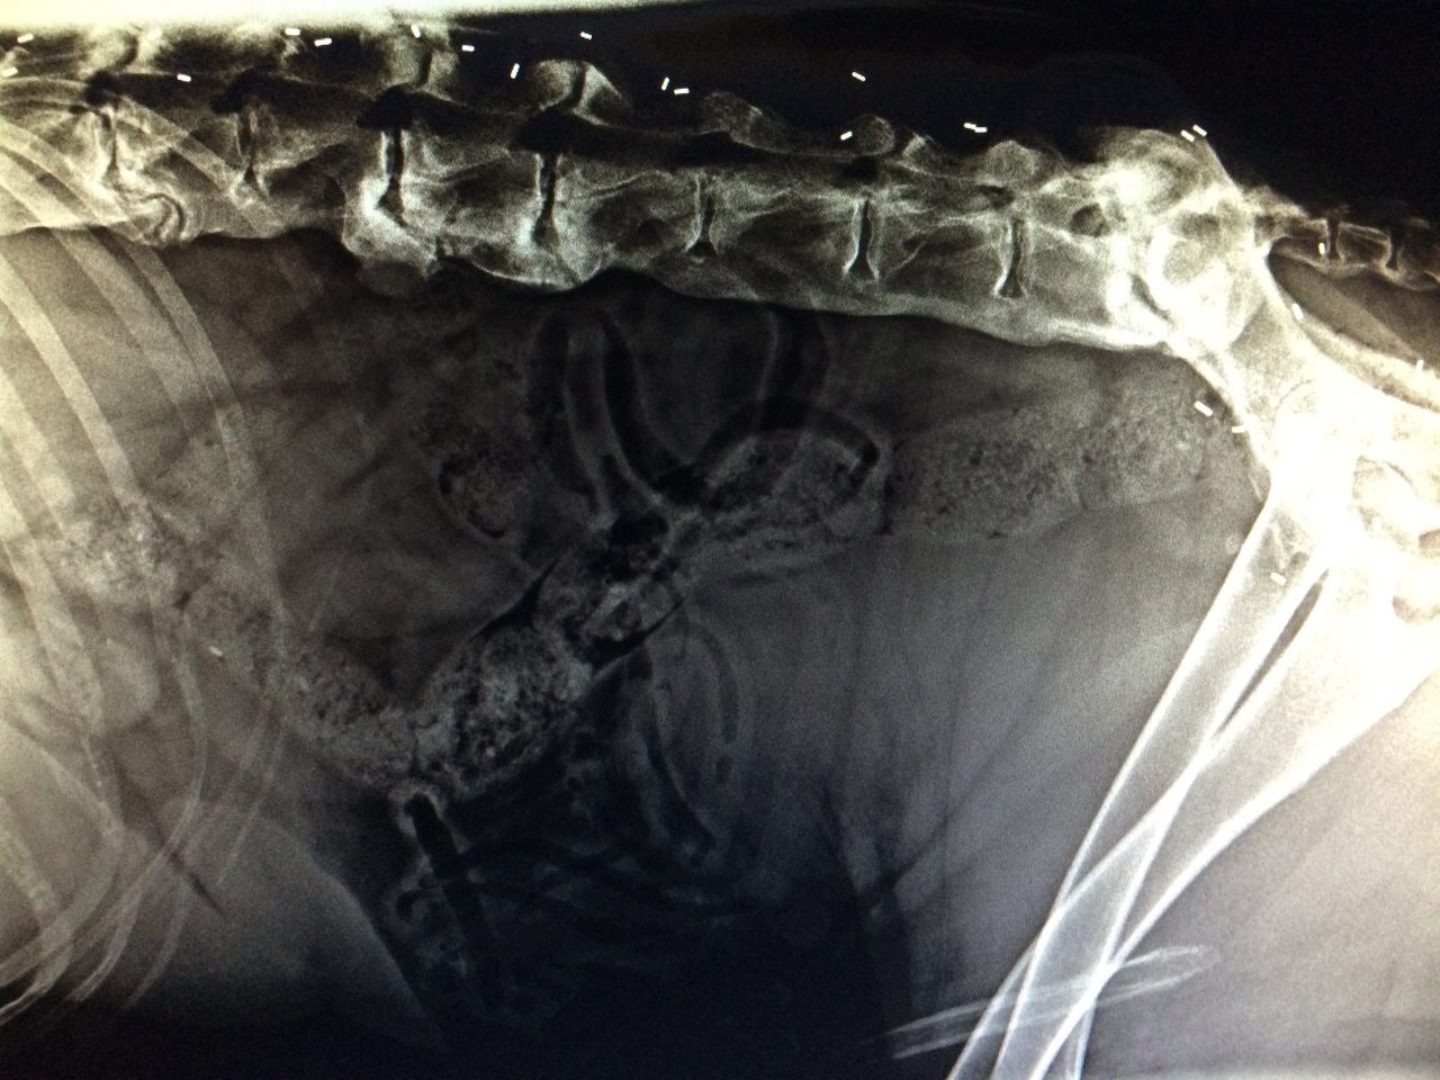

Als der 9-jährige Englische Setter „Pino“ im Oktober 2016 und der 4-jährige Gordon Setter „McFly“ 2011 in meine Praxis kamen, war klar, dass etwas geschehen musste. Mittels der sog. Triggerpunktuntersuchung (Trigger = Auslöser), einer Gangbildanalyse und dem Anfertigen von Röntgenbildern, bestätigte sich die Vermutung auf chronische Schmerzerkrankungen am Bewegungsapparat. Pino litt an einer Hüftgelenkarthrose rechtsseitig, sowie einigen Spondylosen (Veränderungen) der Wirbelsäule, McFly hatte mit einer „Spondylosis deformans“ (degenerative Veränderungen an Wirbelkörpern) zu kämpfen. Nach einem ausgiebigen Beratungsgespräch wurde dann der Termin für eine Goldakupunktur anberaumt.

Goldakupunktur ist eine Therapiemethode, die sich seit den 70er Jahren den Weg in die Behandlungszimmer unserer Tierarztpraxen erkämpft hat und deren Ergebnisse sich meist nur schwer in Worte fassen lassen. Die Goldakupunktur bezeichnet ein Verfahren, in dem mithilfe eines speziell hierfür entwickelten Implantationsbestecks - bestehend aus einer Spritze und einem Hohlkanülenaufsatz - 1-3 mm lange Golddrahtstückchen an und in bestimmten Akupunkturpunkte unter die Haut, bzw. in den Muskel implantiert werden. Der Hund wird einer leichten Schlafnarkose (bis zu 2,5 Stunden) unterzogen. Da das Edelmetall Gold (24 Karat) unglaublich rein ist, wird es von dem Körper nicht abgestoßen oder als körperfremd angesehen. Werden die Goldimplantate an den richtigen Punkten platziert, wird die Schmerzgrenze des Hundes deutlich nach „oben“ verschoben.